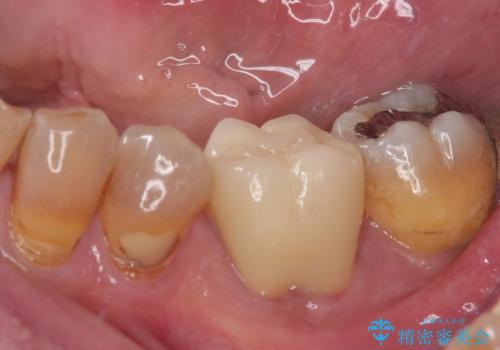

- 上顎大臼歯が食事の度に痛みを感じるとのことで来院された患者様です。

レントゲン写真などで診査を行ったところ、神経組織が壊死し、根尖部周辺の骨に炎症が認められました。

まずは根管治療を行い、症状が消退したことを確認してオールセラミッククラウンにて補綴治療を行うこととしました。